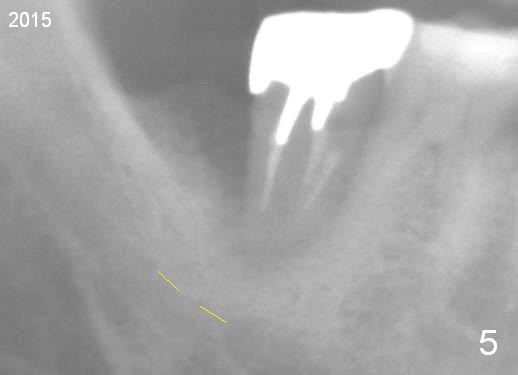

A 44-year-old man has had an asymptomatic distal defect of the tooth #31 for 8 years (Fig.1-5).  Recently there is an acute episode of swelling and pain.  A fistula develops mesiobucally.  Panoramic X-ray films tend to show that the distal defect is deep (Fig.2,5; yellow dashed line: upper border of the Inferior Alveolar Canal).  In addition, the distal defect may be not even buccolingually, as indicated by white and red arrowheads in Fig.3,4.  Following placement of a 6.9x10 mm bone-level implant, a 7.8x4 (4.5) mm cemented abutment is inserted for try in (Fig.6).  When it is fit, it is removed and a cover screw is temporarily placed.  A piece of Osteotape (~10x4 mm) is placed distobuccally or distolingually (depending upon which wall is lower).  A small amount of bone graft is packed between the most coronal portion of the implant and the Osteotape.  The cover screw is then removed and the abutment is re-inserted and tightened by hand.  An immediate provisional is fabricated with well-trimmed margin.  Reline is done if necessary for securely holding bone graft in place.  A new PA is to be taken prior to surgery to determine the extent of the lesion.  Photos are taken to show the mesiobuccal fistula.  Return to Lower Molar Immediate Implant Xin Wei, DDS, PhD, MS 1st edition 04/12/2015, last revision 05/25/2018